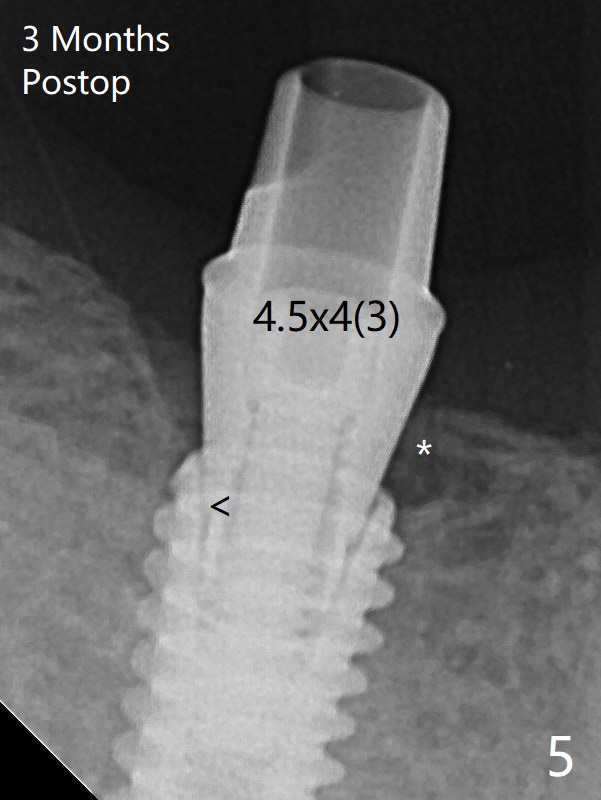

The female patient has limited mouth opening, complicated further by supraerupted opposing tooth. It is difficult to insert point drill and tap drill for #30 implant placement with guide. The former has to be inserted into the sleeve of the guide extraorally; two of them are placed intraorally together, while the tap drill is not used at all. When a 4.5x10 mm implant is placed, it is difficult to use #2 sensor to take PA. Finally a BW is taken with #2 sensor (Fig.1), while a PA is taken with #1 sensor (Fig.2). CT is taken to show clearance of the implant from the Inferior Alveolar Canal (Fig.3,4). To seat healing and later cemented abutments completely, a 5.5 mm profile drill is applied after implant placement; the outline is illustrated by red dashed line in Fig.1''. The elongated mesiolignual cusp of the tooth #3 has to be trimmed after placement of a 6x5 mm healing abutment. In fact trimming prior to osteotomy could solve the mouth opening partially. After removal of the 6x5 mm healing abutment, a 4.5x4(3) mm cemented abutment is incompletely seated (Fig.5 <) apparently due to proximity to the mesial crest (*). With reuse of a 4.6 mm profile drill, the abutment is fully seated (Fig.6), confirmed clinically by more clearance from the opposing tooth (Fig.7). Complete occlusal clearance is obtained by reduction of the opposing cusps without sensitivity since the tooth is nonvital (*). Return to No Deviation Xin Wei, DDS, PhD, MS 1st edition 05/28/2020, last revision 09/04/2020